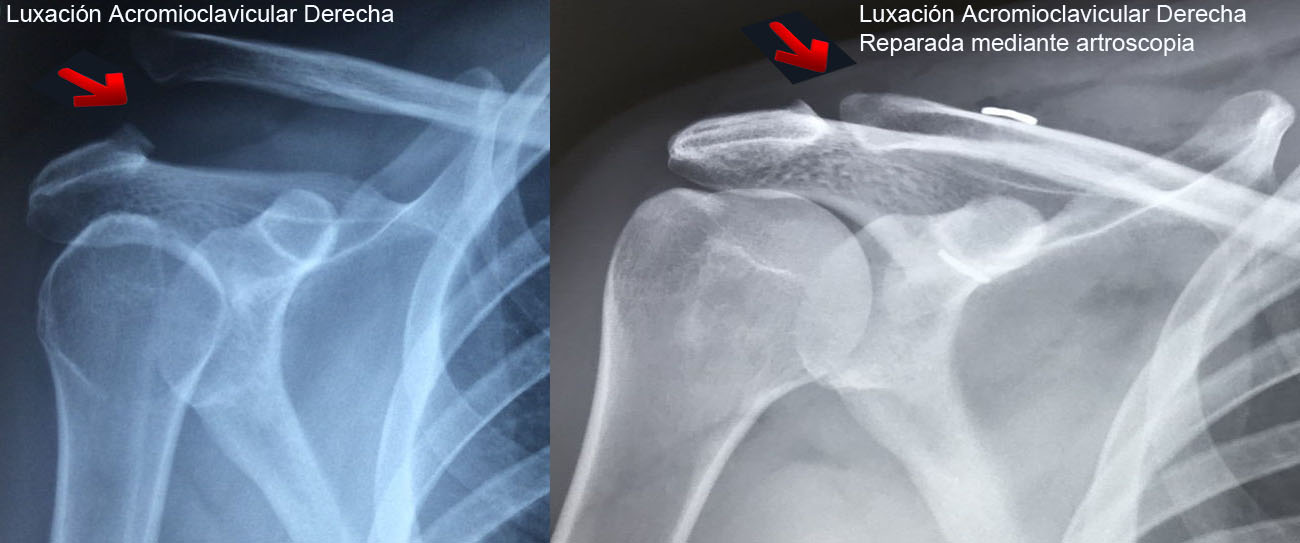

Luxación Acromioclavicular

Es una lesión frecuente en algunos deportes debido a trauma directo en el hombro. Hay una separación del acromion y la clavícula.

El tratamiento dependera del grado de lesión, por lo que la cirugía se reserva para algunos casos específicos.